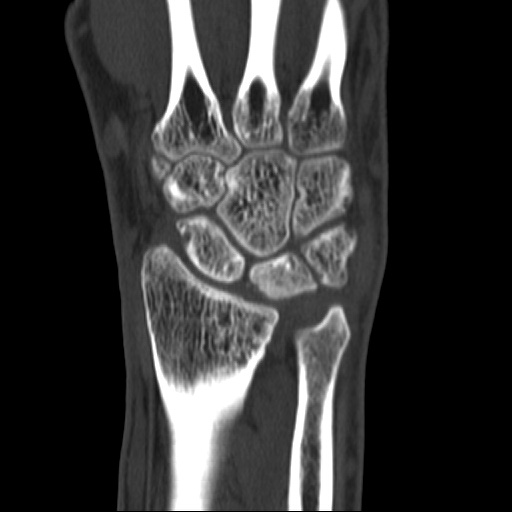

키엔벡병 수술 후

2022.09.16